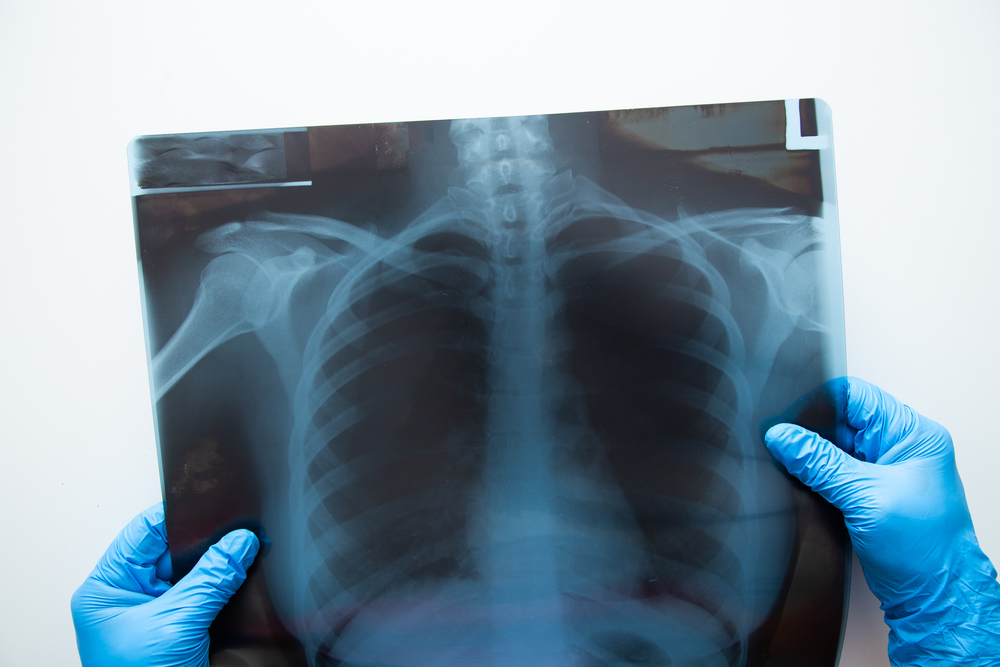

La preparación para una radiografía de tórax representa un proceso sencillo que no requiere medidas complicadas. Este estudio diagnóstico permite evaluar el estado de los pulmones, corazón y otras estructuras torácicas con una metodología simple y rápida.

La radiografía de tórax utiliza radiación ionizante en dosis mínimas para crear imágenes detalladas de los órganos internos. Los especialistas la emplean para diagnosticar diversas condiciones respiratorias y cardíacas, ofreciendo una herramienta fundamental en el diagnóstico médico.

Desarrollo del Procedimiento Radiológico

Posicionamiento durante el Examen

La posición estándar incluye:

- Paciente de pie

- Pecho pegado al receptor de imagen

- Brazos en las caderas

- Proyecciones posteroanterior y lateral